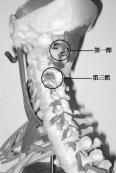

• 頸椎先天融合畸形

早在1912年由Klippel和Feil報道的頸椎先天融合畸形(故又名Klippel-Feil綜合征)系由短頸、后發線低和頸椎活動受限三大臨床特點所組成,僅在伴有臨床癥狀時方需治療。此類患...